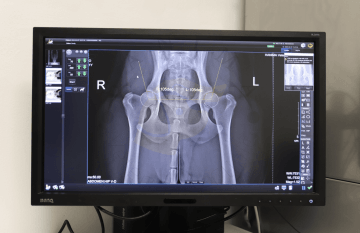

Provádíme kompletní klinická vyšetření s možností vyšetření krevního obrazu, biochemického vyšetření krve a vyšetření moče. Děláme kompletní diagnostiku a terapii v oblasti gastroenterologie (vyjma endoskopie), endokrinologie, diabetologie, nefrologie, urologie, geriatrie. Dále poskytujeme základní diagnostiku a terapii v oblasti kardiologie a pneumologie. Disponujeme vlastním kompletním biochemickým a hematologickým analyzátorem, rentgenem a sonem. Interní medicíně se u nás věnují MVDr. Petra Hlavatá, MVDr. Petra Vojčeková a MVDr. Anna Holubová.

U nás na klinice disponujeme digitálním rentgenem, ultrazvukem značky Vinno A5 (vyšetřujeme zejména játra, ledviny, močový měchýr, dělohu a prostatu), quick PCR testy, hematologickým a biochemickým analyzátorem, rigidním endoskopem a dalším vybavením.